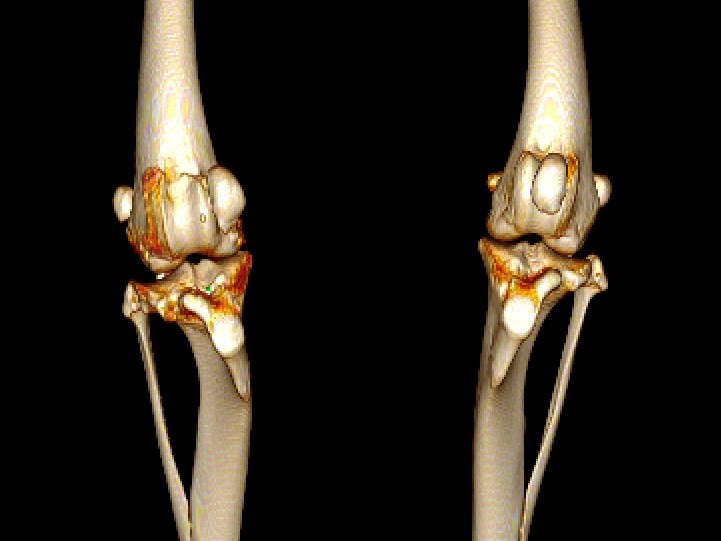

Medial Patellar Luxation (MPL)

Medial patellar luxation (MPL) is a dislocation of the kneecap (patella) toward the inside aspect of the leg. Read more for information on the various surgical options for MPL repair in dogs and what to expect following surgery.